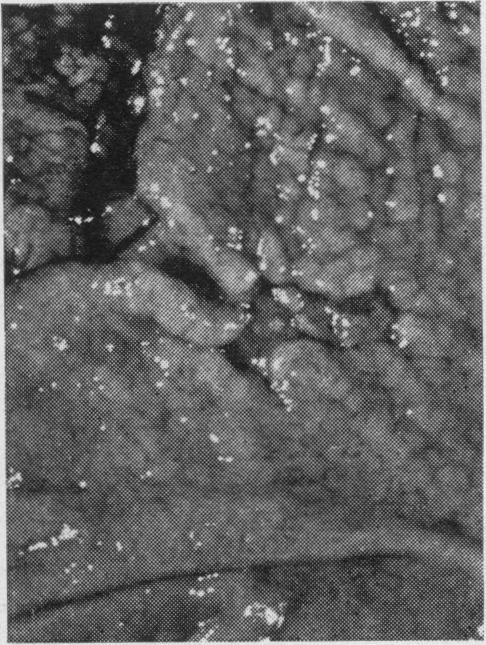

Solanke T F, Kumakura K, Maruyama M, Someya N

Gut. 1969 Jun;10(6):436-42. doi: 10.1136/gut.10.6.436.